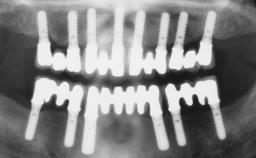

Conventional Loading of Six Implants in the Mandible and Final Restoration with a Full-Arch Metal-Ceramic FDP

# of Implants 6

Type of Implants One-Piece

Attachment One-Piece